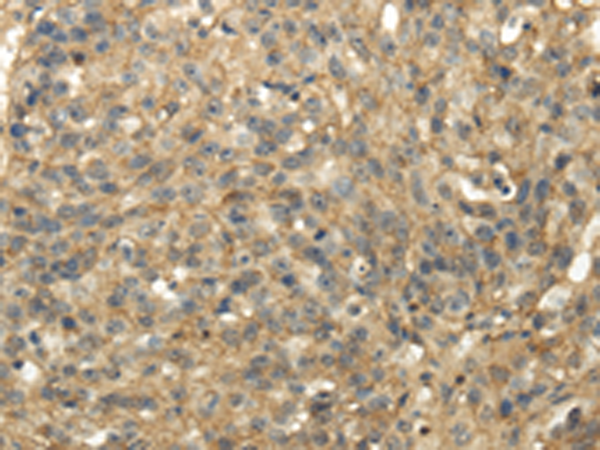

分类: 科研抗体货号: P02106别名:应用: IHC反应种属: Human, Mouse